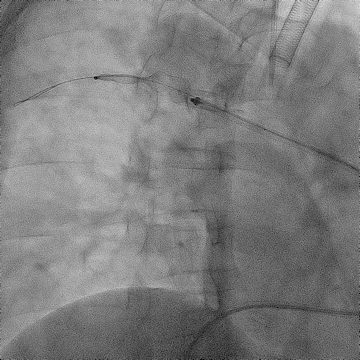

手术过程(二):

使用“Wire In Plug” 技术:在体外释放 20 mm AVP Ⅱ (网盘不解锁),使用穿刺针配合stiff导丝穿过三个网盘,回收至鞘内。